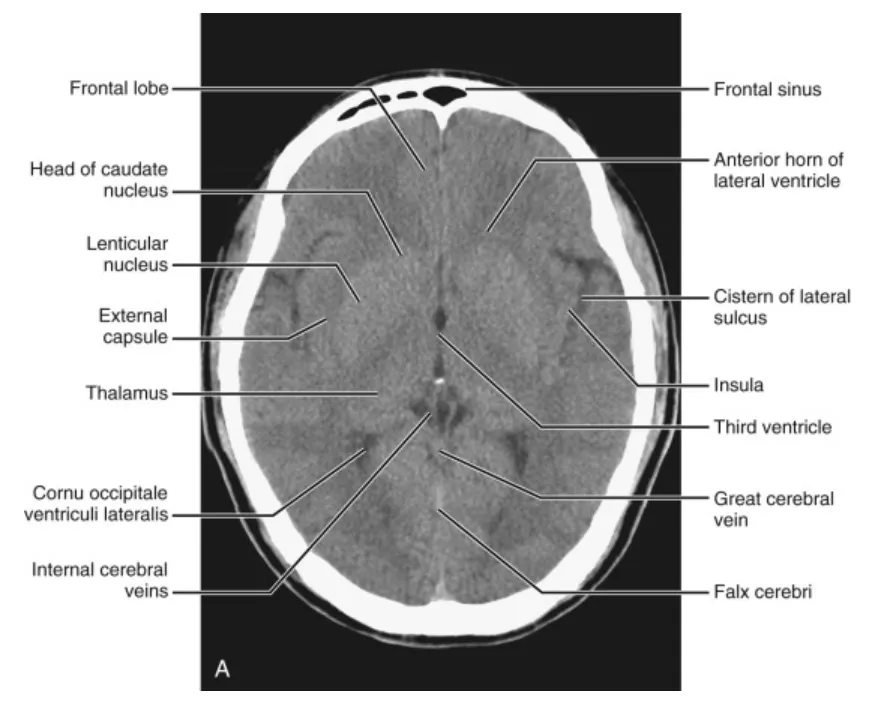

C2. Supratentorial Sections

(1) Third ventricular level

전두엽(frontal lobes)은 내측의 대뇌반구간열(interhemispheric fissure)에 의해 분리되어 보입니다. 표층부에서 실비우스열(sylvian fissures)이 내측으로 연장되어 전두엽을 측두엽(temporal lobe)과 분리합니다. 실비우스열의 내측 표면 안쪽으로 섬피질(insular cortex), 외피막(external capsule), 피각(putamen), 그리고 창백핵(globus pallidus)을 확인할 수 있습니다. 정중선의 제3뇌실(third ventricle)은 측면의 시상(thalamus)에 둘러싸인 틈새 같은 공간으로 보입니다. 제3뇌실 뒤쪽으로 내대뇌정맥(internal cerebral vein), 대대뇌정맥(great vein of Galen), 그리고 소뇌충부(cerebellar vermis)를 볼 수 있습니다. 때때로 제3뇌실 뒤쪽의 송과체(pineal gland)가 이 수준에서 보입니다. 가끔 송과체 석회화 앞쪽에 고삐핵(habenula)의 석회화가 나타나기도 합니다. 측뇌실(lateral ventricle) 내에서 가장 흔하게 석회화되는 맥락얼기(choroid plexus)를 확인할 수 있습니다. 후방으로 후두엽(occipital lobes)이 보입니다.